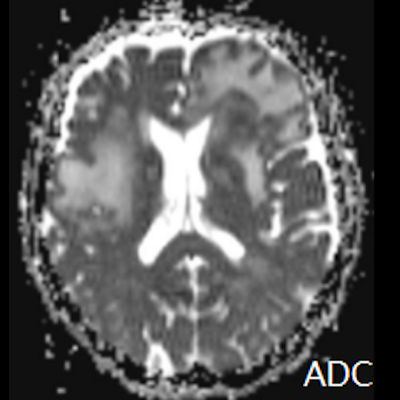

- (C) Difüzyon ağırlıklı görüntülerde sol frontaldeki kitle lezyonunda difüzyon kısıtlama bulgusu (oklar) mevcut olup perfüzyon MRG’de rCBV haritasında belirgin perfüzyon artışı izlenmemektedir (ok).

- MRG’de, lenfomalar tipik olarak T2A sekanslarda hipointens olup DAG’de belirgin difüzyon kısıtlanması gösterirler.

- T2 sinyali belirgin düşük olgularda b=1000 görüntülerde hipointens görünüm izlenebilir ve T2 kararması (T2 black-out) etkisi olarak adlandırılan bu durum yanlış yorumlamalara yol açabilir. Bu nedenle gerçek difüzyon kısıtlamasını değerlendirmede ADC haritaları daha güvenilirdir.

- Perfüzyon MRG’de düşük-orta düzey CBV değerleri izlenir. Lenfomalarda düşük CBV değerleri, kötü prognoz göstergesidir.